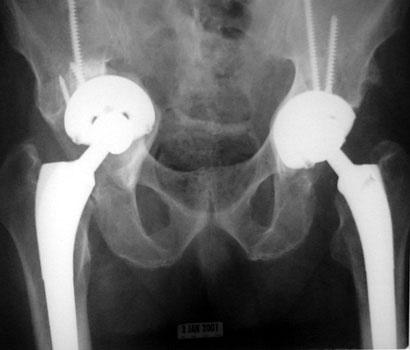

LooseningAs pain and disability due to loosening become severe enough to require revision arthroplasty, abnormalities in the binding of the cement to the bone or prosthesis are almost always visible radiographically. Radiographic abnormalities include:

Absence of these findings requires consideration of other sources for painful arthroplasty. INTERFACE WIDENING

INTERFACE WIDENING

LOOSENING WITH FEMORAL COMPONENT IN VARUS LOOSENING